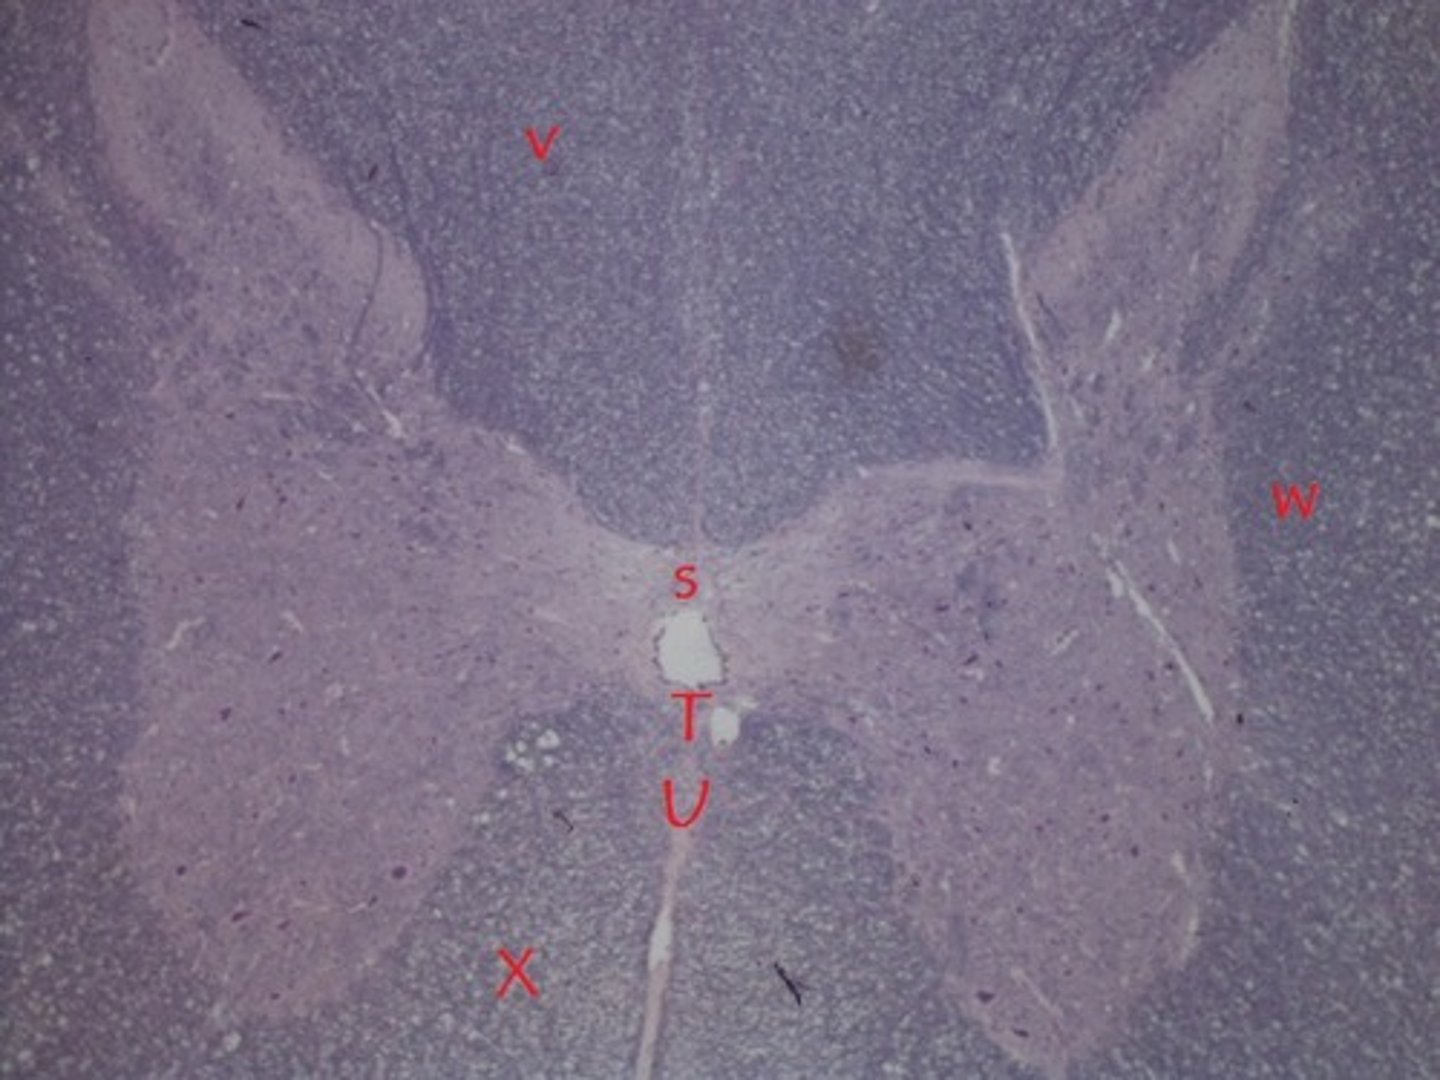

central canal

B

anterior median fissure

C

anterior gray horn

D

dorsal gray horn

E

posterior white column

V

lateral white column

W

anterior white column

X